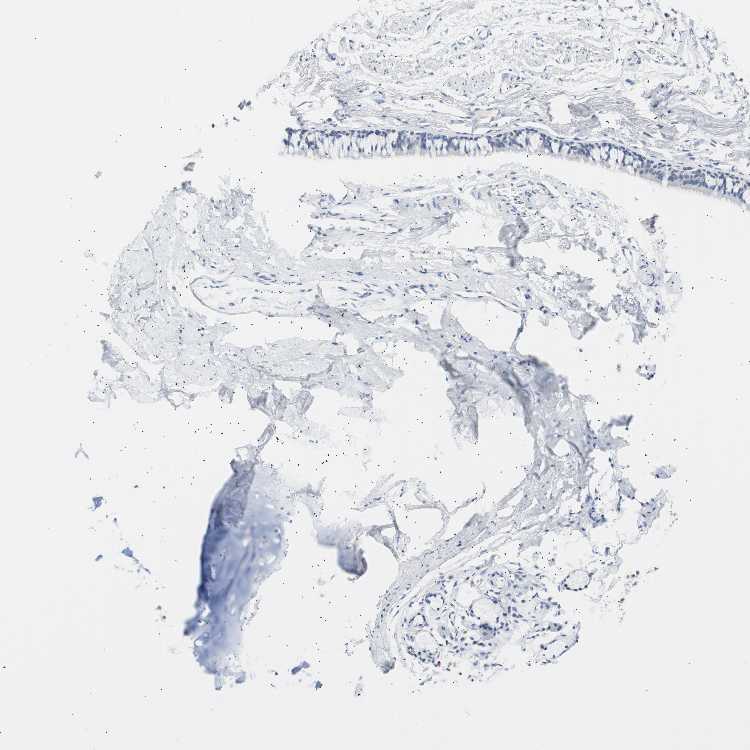

SOFT TISSUE 1 - Antibody stainingi

Antibody staining in the annotated cell types in the current human tissue is reported as not detected, low, medium, or high, based on conventional immunohistochemistry profiling in selected tissues. This score is based on the combination of the staining intensity and fraction of stained cells.

Each image is clickable and will lead to virtual microscopy that enables deeper exploration of all samples and also displays staining intensity scores, fraction scores and subcellular localization as well as patient and tissue information for each sample.

Antibody HPA006884Antibody HPA006885Antibody CAB002452

Chondrocytes Not detectedNot detectedNot detected

Fibroblasts Not detectedNot detectedNot detected

Peripheral nerve Not detectedNot detectedNot detected